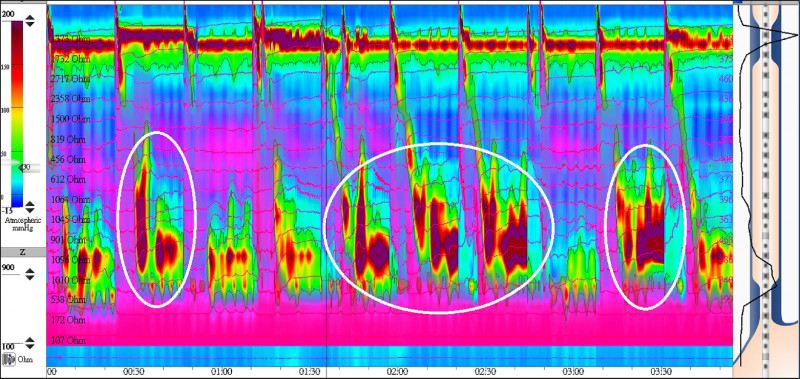

張先生經過他人介紹,到我的門診就醫。在跟他討論的過程中,我判斷這可能是食道痙攣,是一種食道蠕動功能異常。於是我幫他安排了一種特殊檢查,叫做高解析度食道壓力檢測(High-resolution impedance manometry,簡稱HRIM)。

這個檢測,是從鼻孔放入一條佈滿多個壓力檢測點的導管進入食道,並藉由躺姿及坐姿多次小口喝水,來了解食道收縮情形。做完這個檢查後發現張先生罹患了一種罕見的食道蠕動異常,叫做電鑽型食道(Jackhammer esophagus)(圖2)。根據檢測結果,我們調整用藥,給予高血壓常用的鈣離子通道阻斷劑及硝酸鹽藥物使食道肌肉舒張,一個多月後,症狀幾乎消失9成以上。張先生終於可以好好吃飯了。

高解析壓力檢測 精準診斷異常

至於診斷方面,傳統胃鏡及食道攝影診斷率低,要確診唯有靠這種高解析度食道壓力檢測才有辦法診斷。